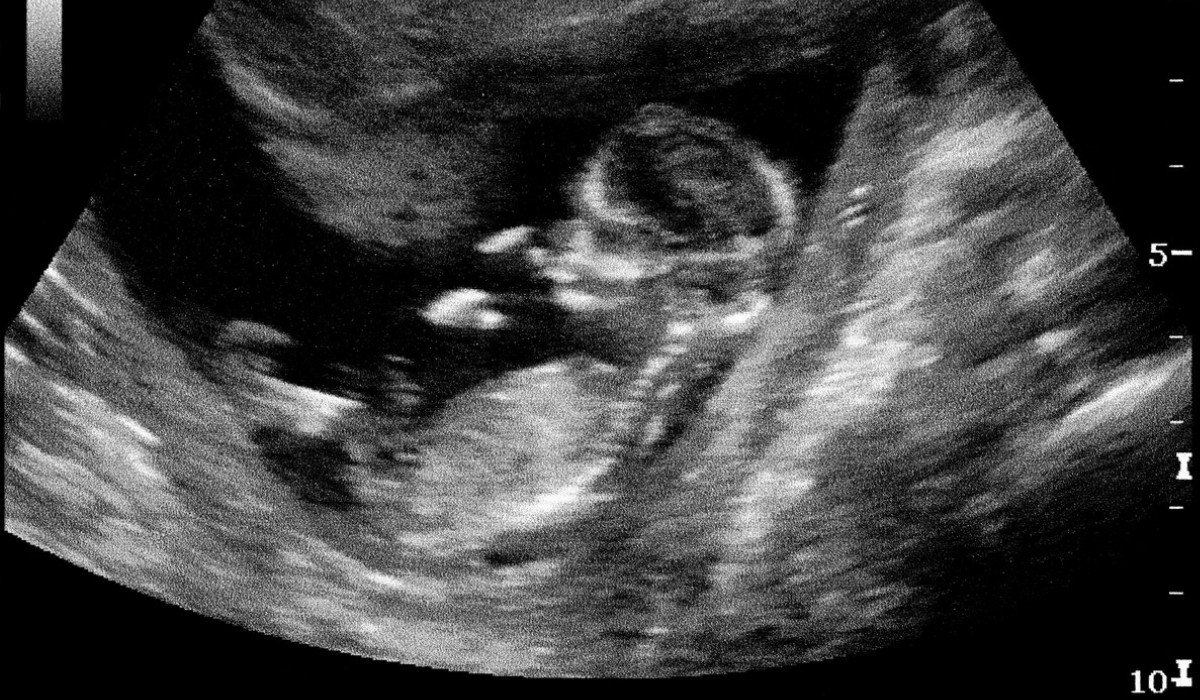

Dispariția lui Mircea Lucescu, unul dintre cei mai mari antrenori din istoria fotbalului, scoate la lumină pericolul unor afecțiuni care acționează tăcut. AVC-ul ischemic și tromboembolismul pulmonar sunt boli care pot lovi fulgerător și care, din păcate, afectează tot mai des și persoane tinere.